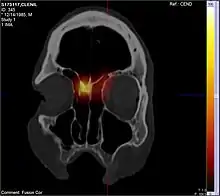

CT scan images after application of radioactive laced nasal steroids using long nozzle. Note the reach of the medication into the area where nasal polyps originate

Endoscopic sinus surgery, advocated and popularized by Professor Stammberger, is often very effective for most people, providing rapid symptom relief. Endoscopic sinus surgery is minimally-invasive and is done entirely through the nostril with the help of a camera. Surgery should be considered for those with complete nasal obstruction, uncontrolled runny nose, nasal deformity caused by polyps or continued symptoms despite medical management.[7] Surgery serves to remove the polyps as well as the surrounding inflamed mucosa, open obstructed nasal passages, and clear the sinuses. This not only removes the obstruction caused by the polyps themselves, but allows medications such as saline irrigations and topical steroids to become more effective.[18] It has been suggested that one of the main objectives in sinus surgery for polyps is to allow delivery of the steroids into those areas of the sinuses where polyps develop, namely, the ethmoid sinuses. Specially designed long nozzles had been developed to use postoperatively to deliver steroids into those areas after sinus surgery for polyps.[19]